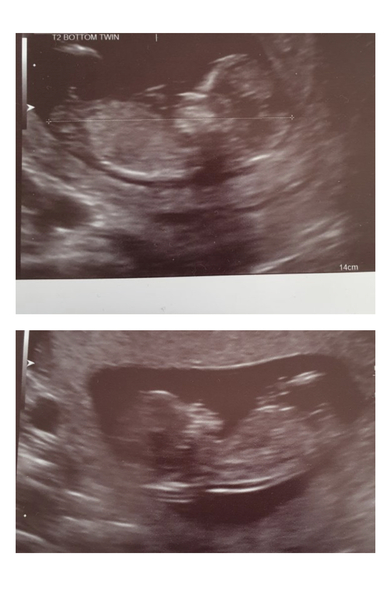

Hi ladies just popped in with a little update and to say thank you so much and farewell to you all . I really do wish the very best of luck to all you lovely people Wether you already have your bfp or are still patiently waiting for that first sign of your rainbow appearing 🌈 just reading your stories and the amazing way you all support each other on here has really helped get me through the last few months . My 12 week scan this morning went well and both twins are growing nicely and as expected . I was delighted to see they have their own sacs this time round 😁🙏 but as they are sharing a placenta there is still a very high risk of complications going forward . Going to be a long climb up the mountain for us but currently heading in the right direction which is all I can hope for at this point . Next mile stone will be passing the 16 plus 2 point were I Previously lost my Twin boys 💔 . For this reason I’ve made the decision to come off all parenting forums and social media for a while and focus only on relaxation and spending quality time with my girls over the next month or so to help me cope with the overwhelming fear / anxiety and most Importantly help me stay away from google . In the nicest possible way I can only hope to never be rejoining you but truly appreciate the special safe space you’ve all created here and hope that If I do have a need to return that your all long gone having graduated to your due date clubs . Lots of love and positive baby dust to you all 💞